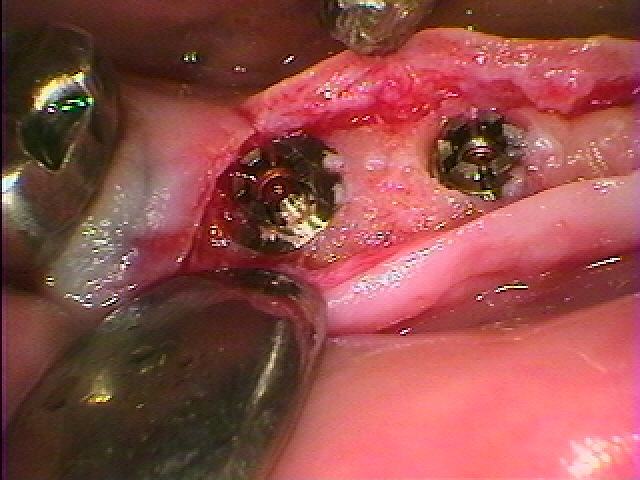

欠損部にはこのようにインプラントを埋入しています

埋入後になります

コーティング面がしっかりと隠れるように埋入しています